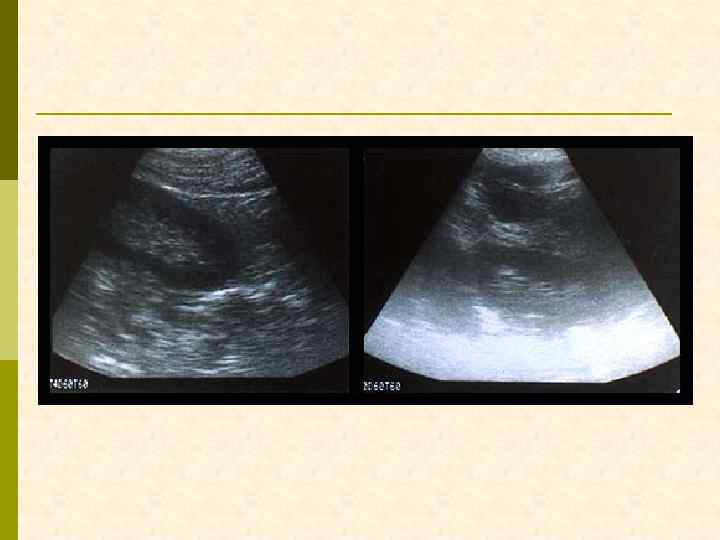

УЛЬТРАЗВУКОВОЕ ИССЛЕДОВАНИЕ ПЕРЕД ВЫПОЛНЕНИЕМ НЕФРОБИОПСИИ

ЛОКАЛИЗАЦИЯ БИОПСИОННОЙ ИГЛЫ ПРИ УЛЬТРАЗВУКОВОМ ИССЛЕДОВАНИИ